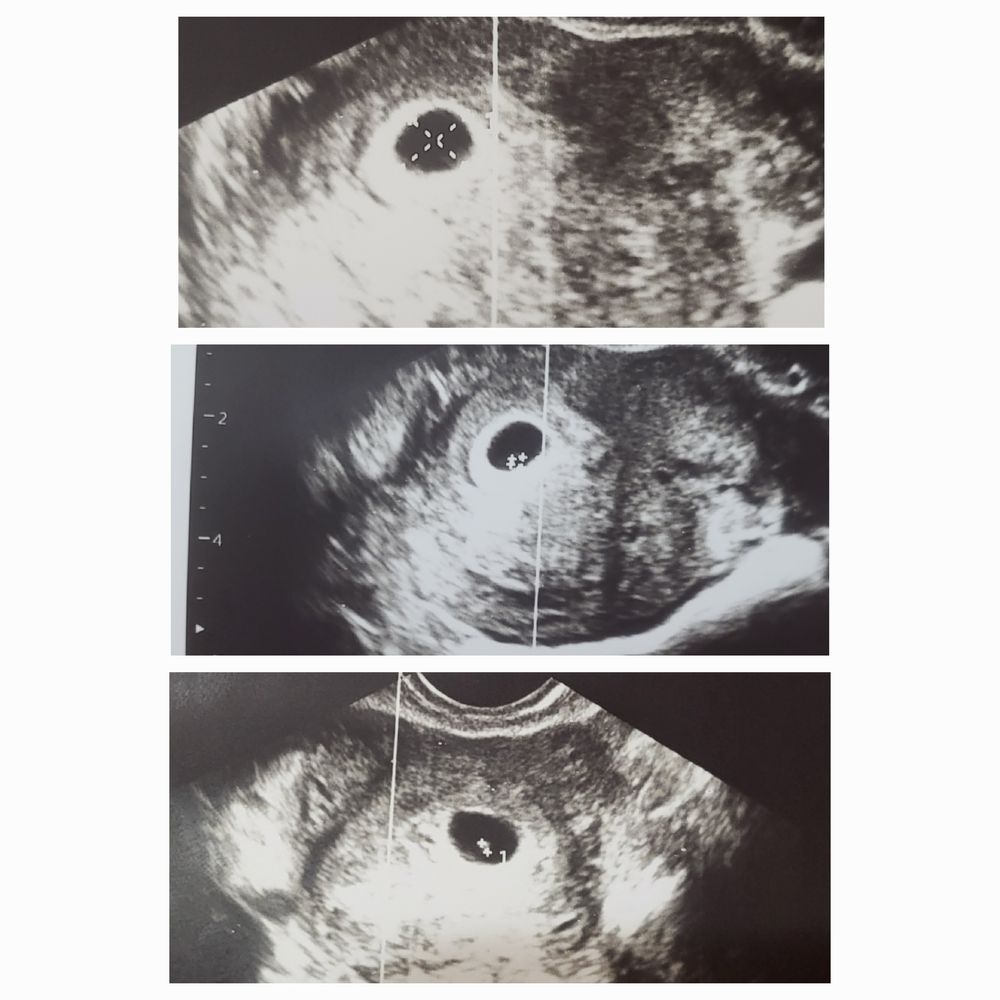

Динамика хгч 🤰❣️+ первое узи

Динамика хгч Динамика ХГЧ, ощущения и узи